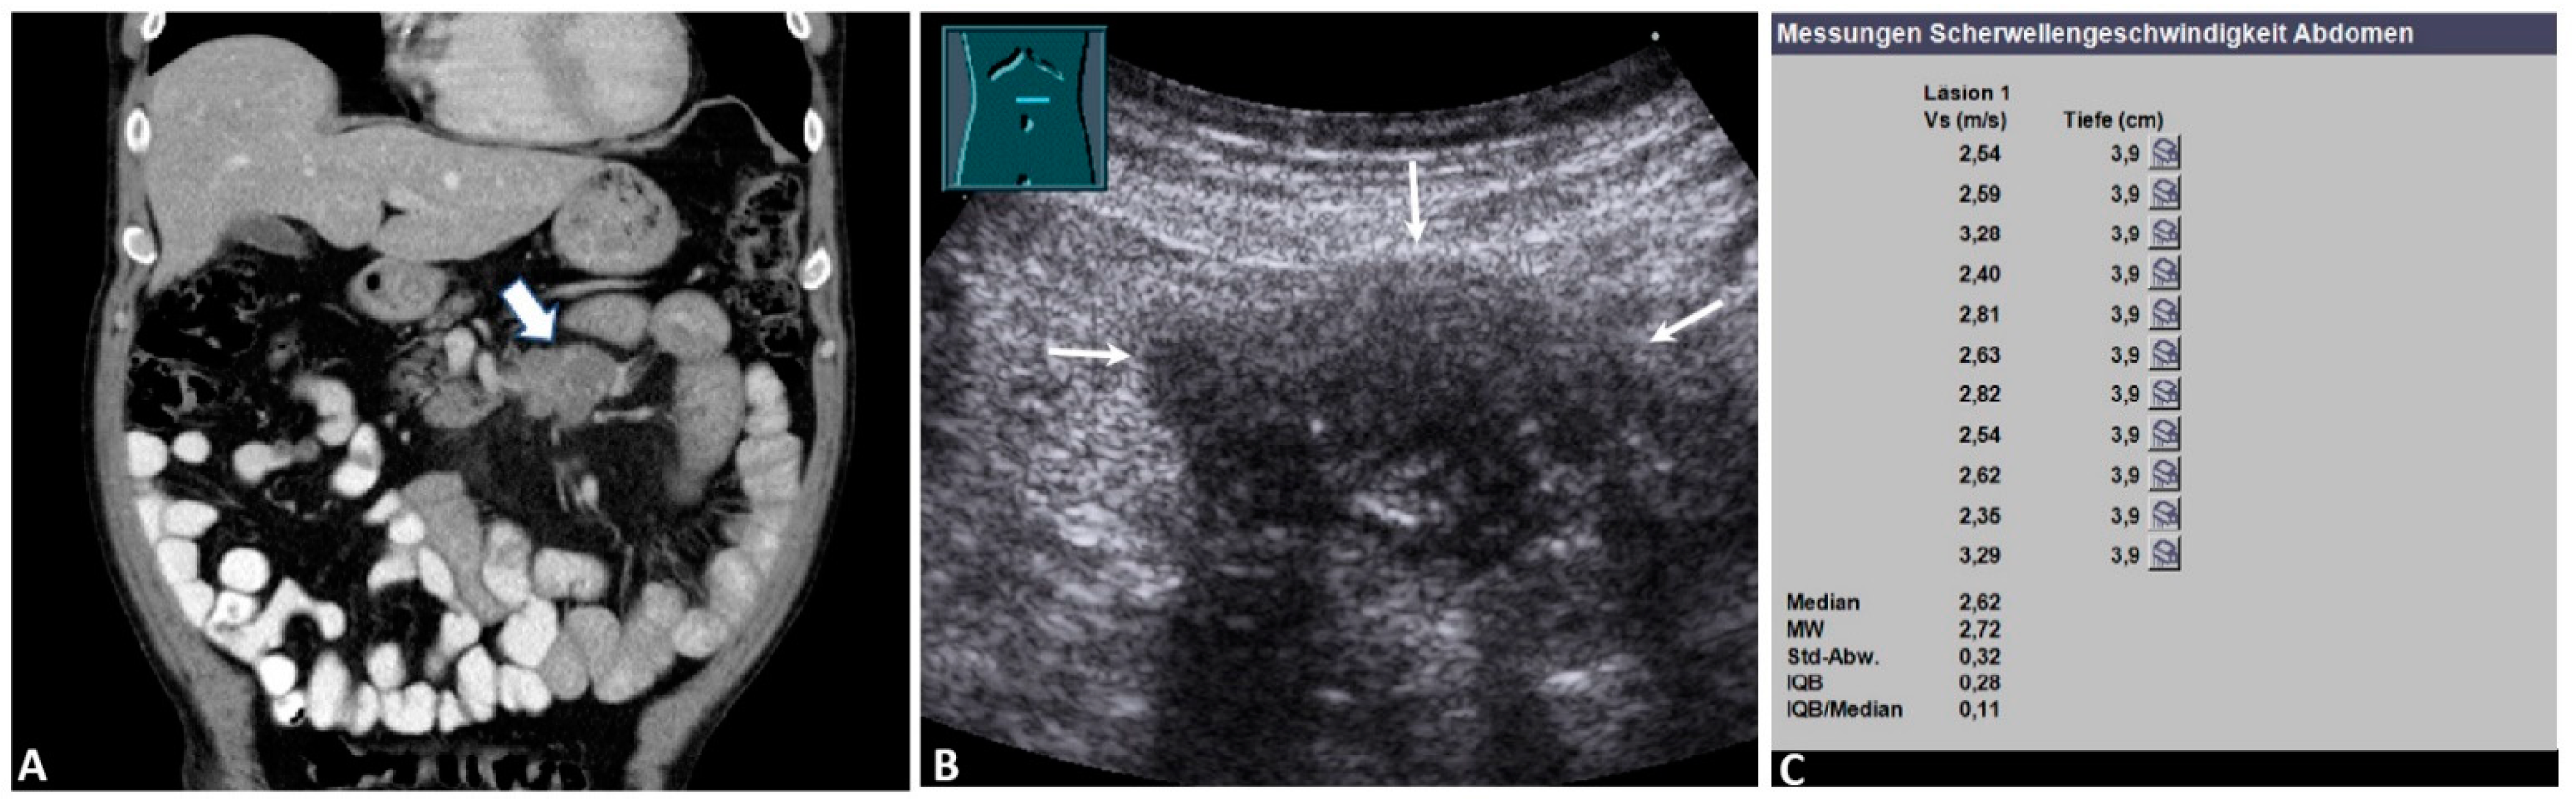

| mMMs | 32 | 2.76 ± 1.01 | 0.77 | 4.22 | 4.25 ± 0.80 |

| Non-hematological | 17 | 2.79 ± 1.03 | 1.18 | 4.22 | 4.07 ± 0.80 |